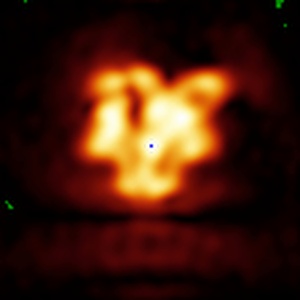

HIV-1 BaL Env in complex with CD4 mimetic CJF-III-288 and 17b IgG

Subtomogram averaging21.5 Å

The asymmetric opening of HIV-1 Env by a potent CD4 mimetic enables anti-coreceptor binding site antibodies to mediate ADCC.